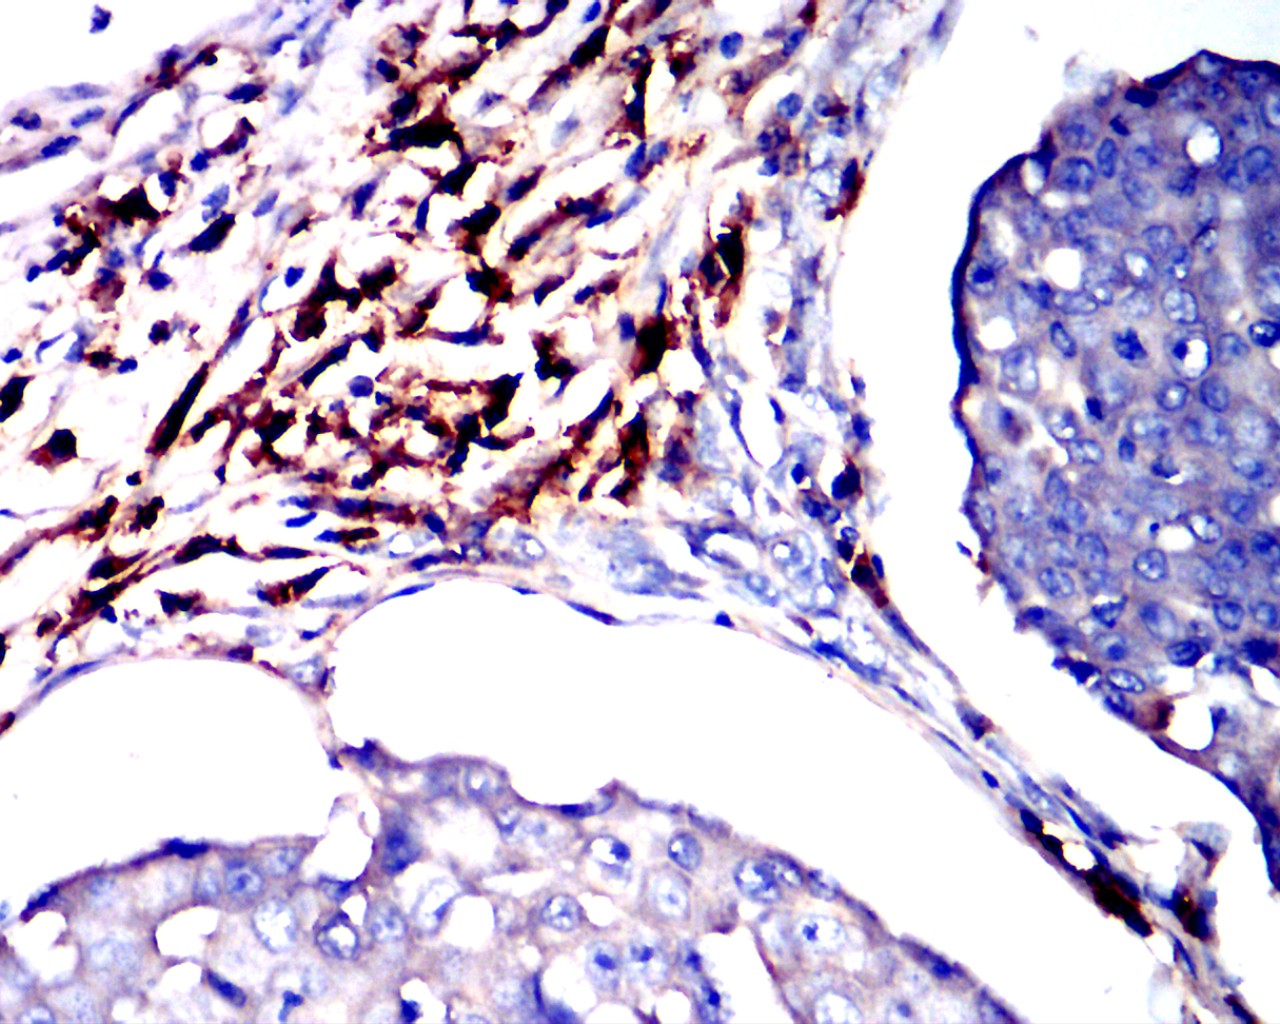

分类: 科研抗体货号: 32473别名: T10;ADPRC 1;ADPRC1;cADPR1应用: IHC反应种属: Human